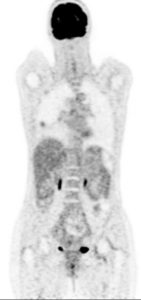

Lymphome de MALT pulmonaire – TEP FDG

Exploration d’un nodule en verre dépoli de découverte fortuite chez une patiente de 53 ans. Pas de tabagisme.

Hypermétabolisme isolé de la plage en verre dépoli du segment apical du lobe inférieur droit (SUV=2.6).

Pas d’hypermétabolisme ganglionnaire.

Biopsie : Lymphome de MALT

Localisation pulmonaire d’un lymphome de MALT (mucosa associated lymphoid tissue).

LMNH de bas grade habituellement avide en FDG.